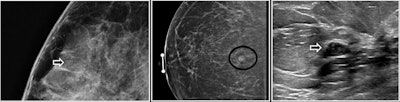

Examples of FEA on abnormal screening mammograms.

Examples of FEA on abnormal screening mammograms.When the authors only analyzed studies that reported cancer type, FEA had an upgrade rate of 1% to invasive cancer and 2% to DCIS. They also observed stable upgrade rates over time.